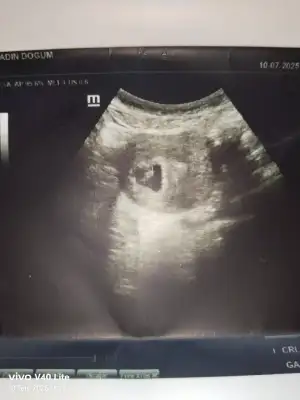

Ay bence kız10+2 karından ultrason bana da bakar mısınız lütfen aşırı merak ediyorum

Bizede bakarmisiniz10+2 karından ultrason bana da bakar mısınız lütfen aşırı merak ediyorum